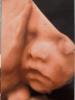

Покажите пожалуйста фоточки ваших малышей в 21 - 22 недели 🥹❤️ Какой был вес и рост?

600 грам весил

@am.luo, на 22 , узи щас поищу

Фото УЗИ вы хотите?